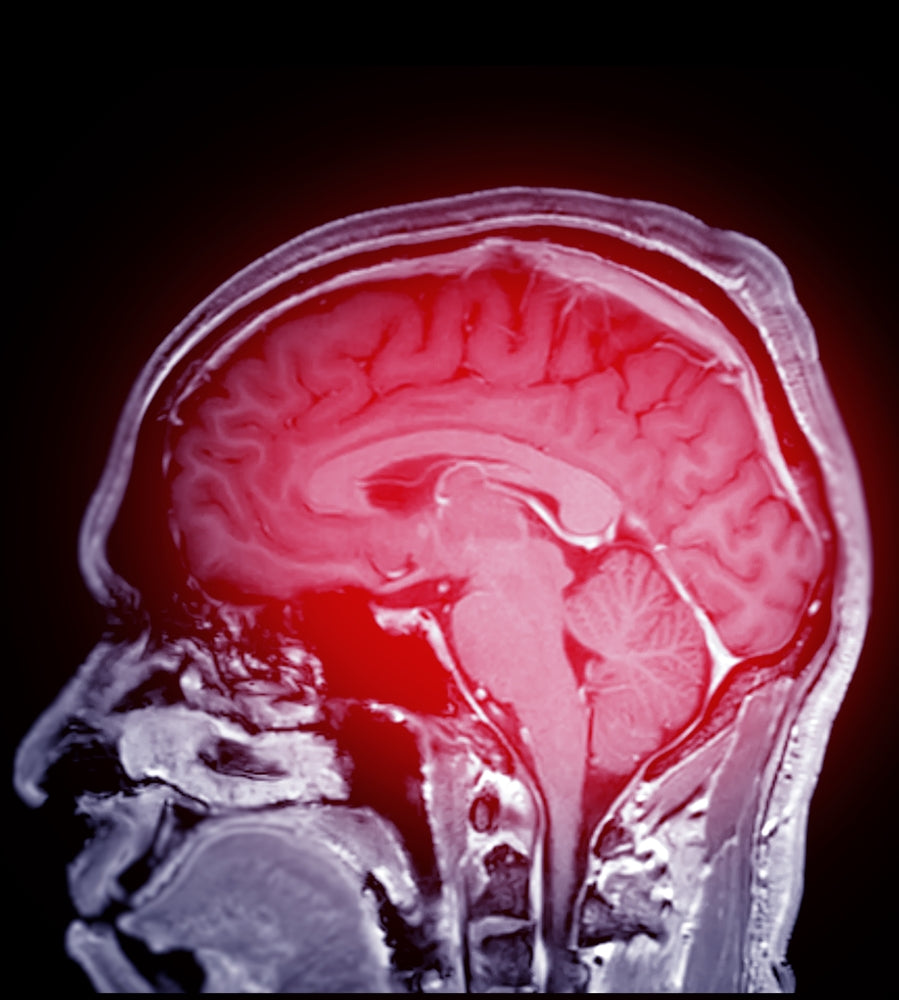

Stroke

Hyperbaric oxygen therapy can significantly enhance stroke recovery by delivering high concentrations of oxygen to damaged brain tissue, promoting neural repair and reducing inflammation. This innovative treatment has shown promising results in improving motor function and cognitive outcomes for stroke survivors when integrated into comprehensive rehabilitation programs.